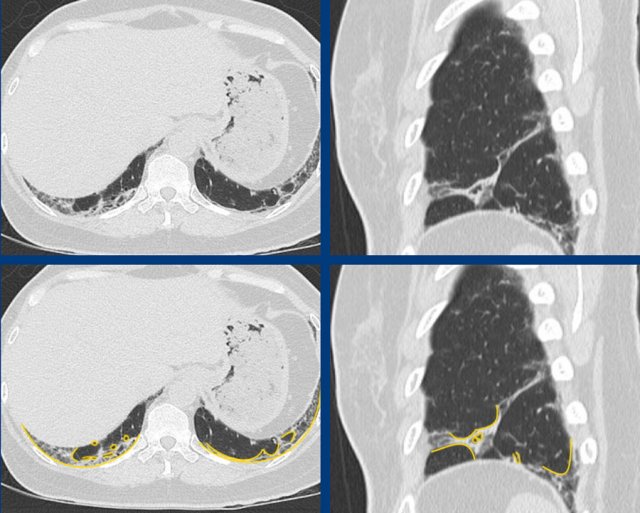

The images show fibrotic lung disease with distortion of the secondary lobule, volume loss and traction bronchiectasis (green is normal, yellow is abnormal).

The images show examples of non-fibrotic reticulation due to interstitial thickening in pulmonary edema (A), lymphangitic carcinomatosis (B), and eosinophilic infiltration in eosinophilic granulomatis with polyangitis [EGPA, former Churg-Strauss syndrome] (C).